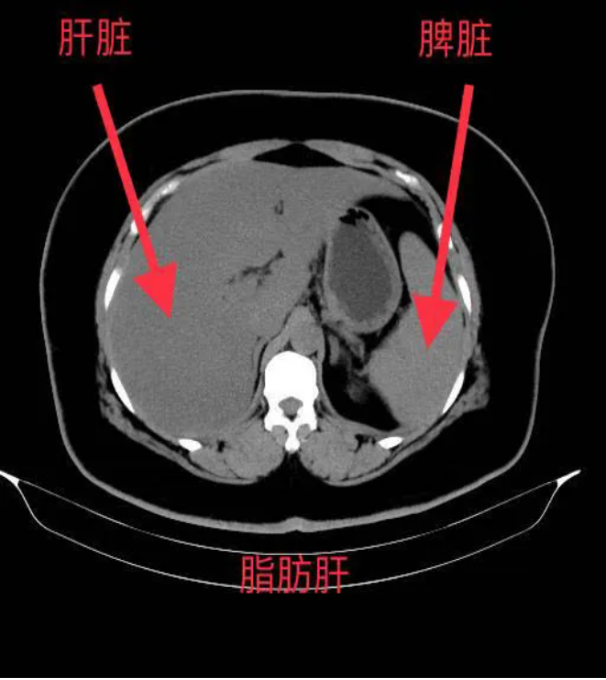

*肝脏密度降低:脂肪的CT值低于正常肝组织,因此脂肪肝在CT图像上表现为肝脏密度普遍降低,与脾脏密度相比更加明显。

*肝内血管模糊:由于脂肪的堆积,肝内血管在CT图像上会变得模糊不清,甚至消失。

*肝脾CT值比值:正常情况下,肝脏CT值高于脾脏,而脂肪肝患者的肝脾CT值比值会降低,甚至出现反转。